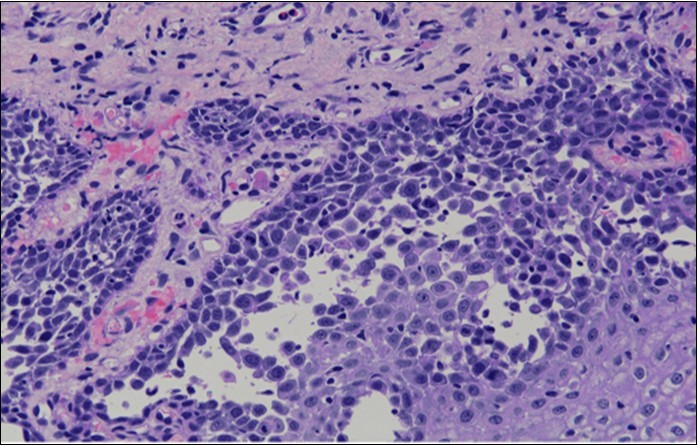

HPV test was negative for high risk subtypes of HPV. The punch biopsy specimen comprised a piece of inflamed cervical tissue in which the transformation zone was represented. The cervical tissue was covered by metaplastic and hyperplastic squamous epithelium showing intraepidermal suprabasal blister formation with acantholysis. Well vascularised dermal papillae lined residual basal cells giving rise to a tombstone appearance were present. There was no evidence of HPV, CIN, CGIN or invasive malignancy.

She was discussed at the hospital cyto-pathology conference to clarify the diagnosis. The original cytological smear specimen was reviewed, with features of bi-nucleation and koilocytosis consistent with LSIL. The cervical biopsy was also reviewed, confirming typical features suggestive of cervical pemphigus. (Figure 4a, Figure 4b, Figure 4c)

Figure 4a.Cervical tissue showing intraepidermal and supra-basal blister formation.

Figure 4b.Prominent acantholysis identified

Figure 4c.Well vascularised dermal papillae with residual basal layer giving rise to tombstone appearance